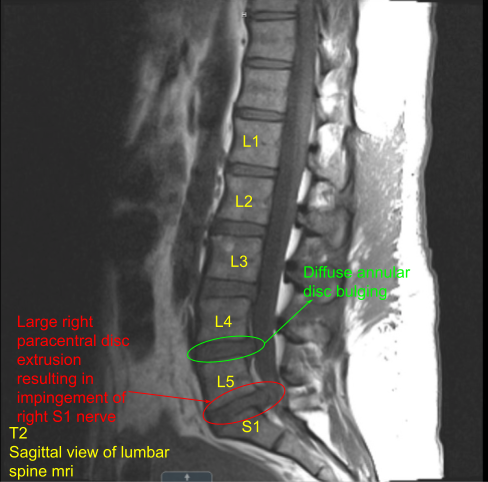

A patient presented with severe radicular pain on the right lower extremity, which was not relieved with conservative treatment and the patient was admitted to the hospital where a Magnetic resonance imaging (MRI) was done, which showed an extruded disc of L5-S1. The patient was also having weakness in the S1 myotome on the right.